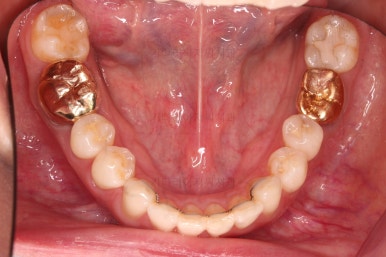

아랫니 부분교정이 끝났고요.

어금니도 원위치로 많이 갔네요.

아랫니 부분교정과 어금니 부분교정은 비교적 조기에 끝났으나(7개월) 임플란트가 생각보다 오래 걸렸습니다.

적절한 공간 확보 이후 해당 부분의 뼈가 너무 얇아 임플란트를 하기에 부적절했던거죠.

상악동 거상술 + 골이식을 광범위하게 꽤 많은 양을 하고, 한참을 기다립니다.

이후에 적절한 시기에 임플란트 식립을 하고 보철을 하고 마무리를 합니다.

치료 종료시의 모습인데요.

임플란트가 잘 들어갔고 아래 앞니도 원하는 모습으로 잘 배열이 되었습니다.